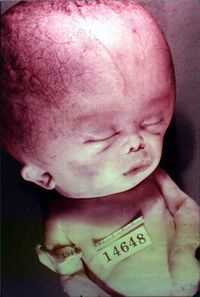

| استسقاء المخ كما يظهر في الأشعة المقطعية على المخ. المناطق السوداء في منتصف المخ هي تضخم غير طبيعي ومملوء بالسوائل. | |